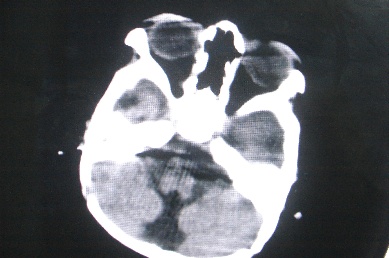

以下是引用余辉在2007-4-30 16:36:00的发言:[br]呵呵,图片不行啊,双肺弥漫斑片状影。右肺门增大,结构模糊。左侧脑室前部室管膜下可见团块状高密度影,周围有低密度环带,左额叶呈大片状低密度改变,略呈楔形,累及灰白质,局部脑沟裂消失,右额叶脑白质亦可见点状病灶(不知是伪影还是真病灶)脑室系统明显扩张,有全脑脑萎缩征象,不知其病史,暂考虑1双肺结核,左额叶结核性脑炎,(左侧脑室前部室管膜下肉芽?出血?)合并脑积水脑萎缩(左额叶低密度区不排除脑梗塞改变)2双肺非特异性炎症合并化脓性脑炎